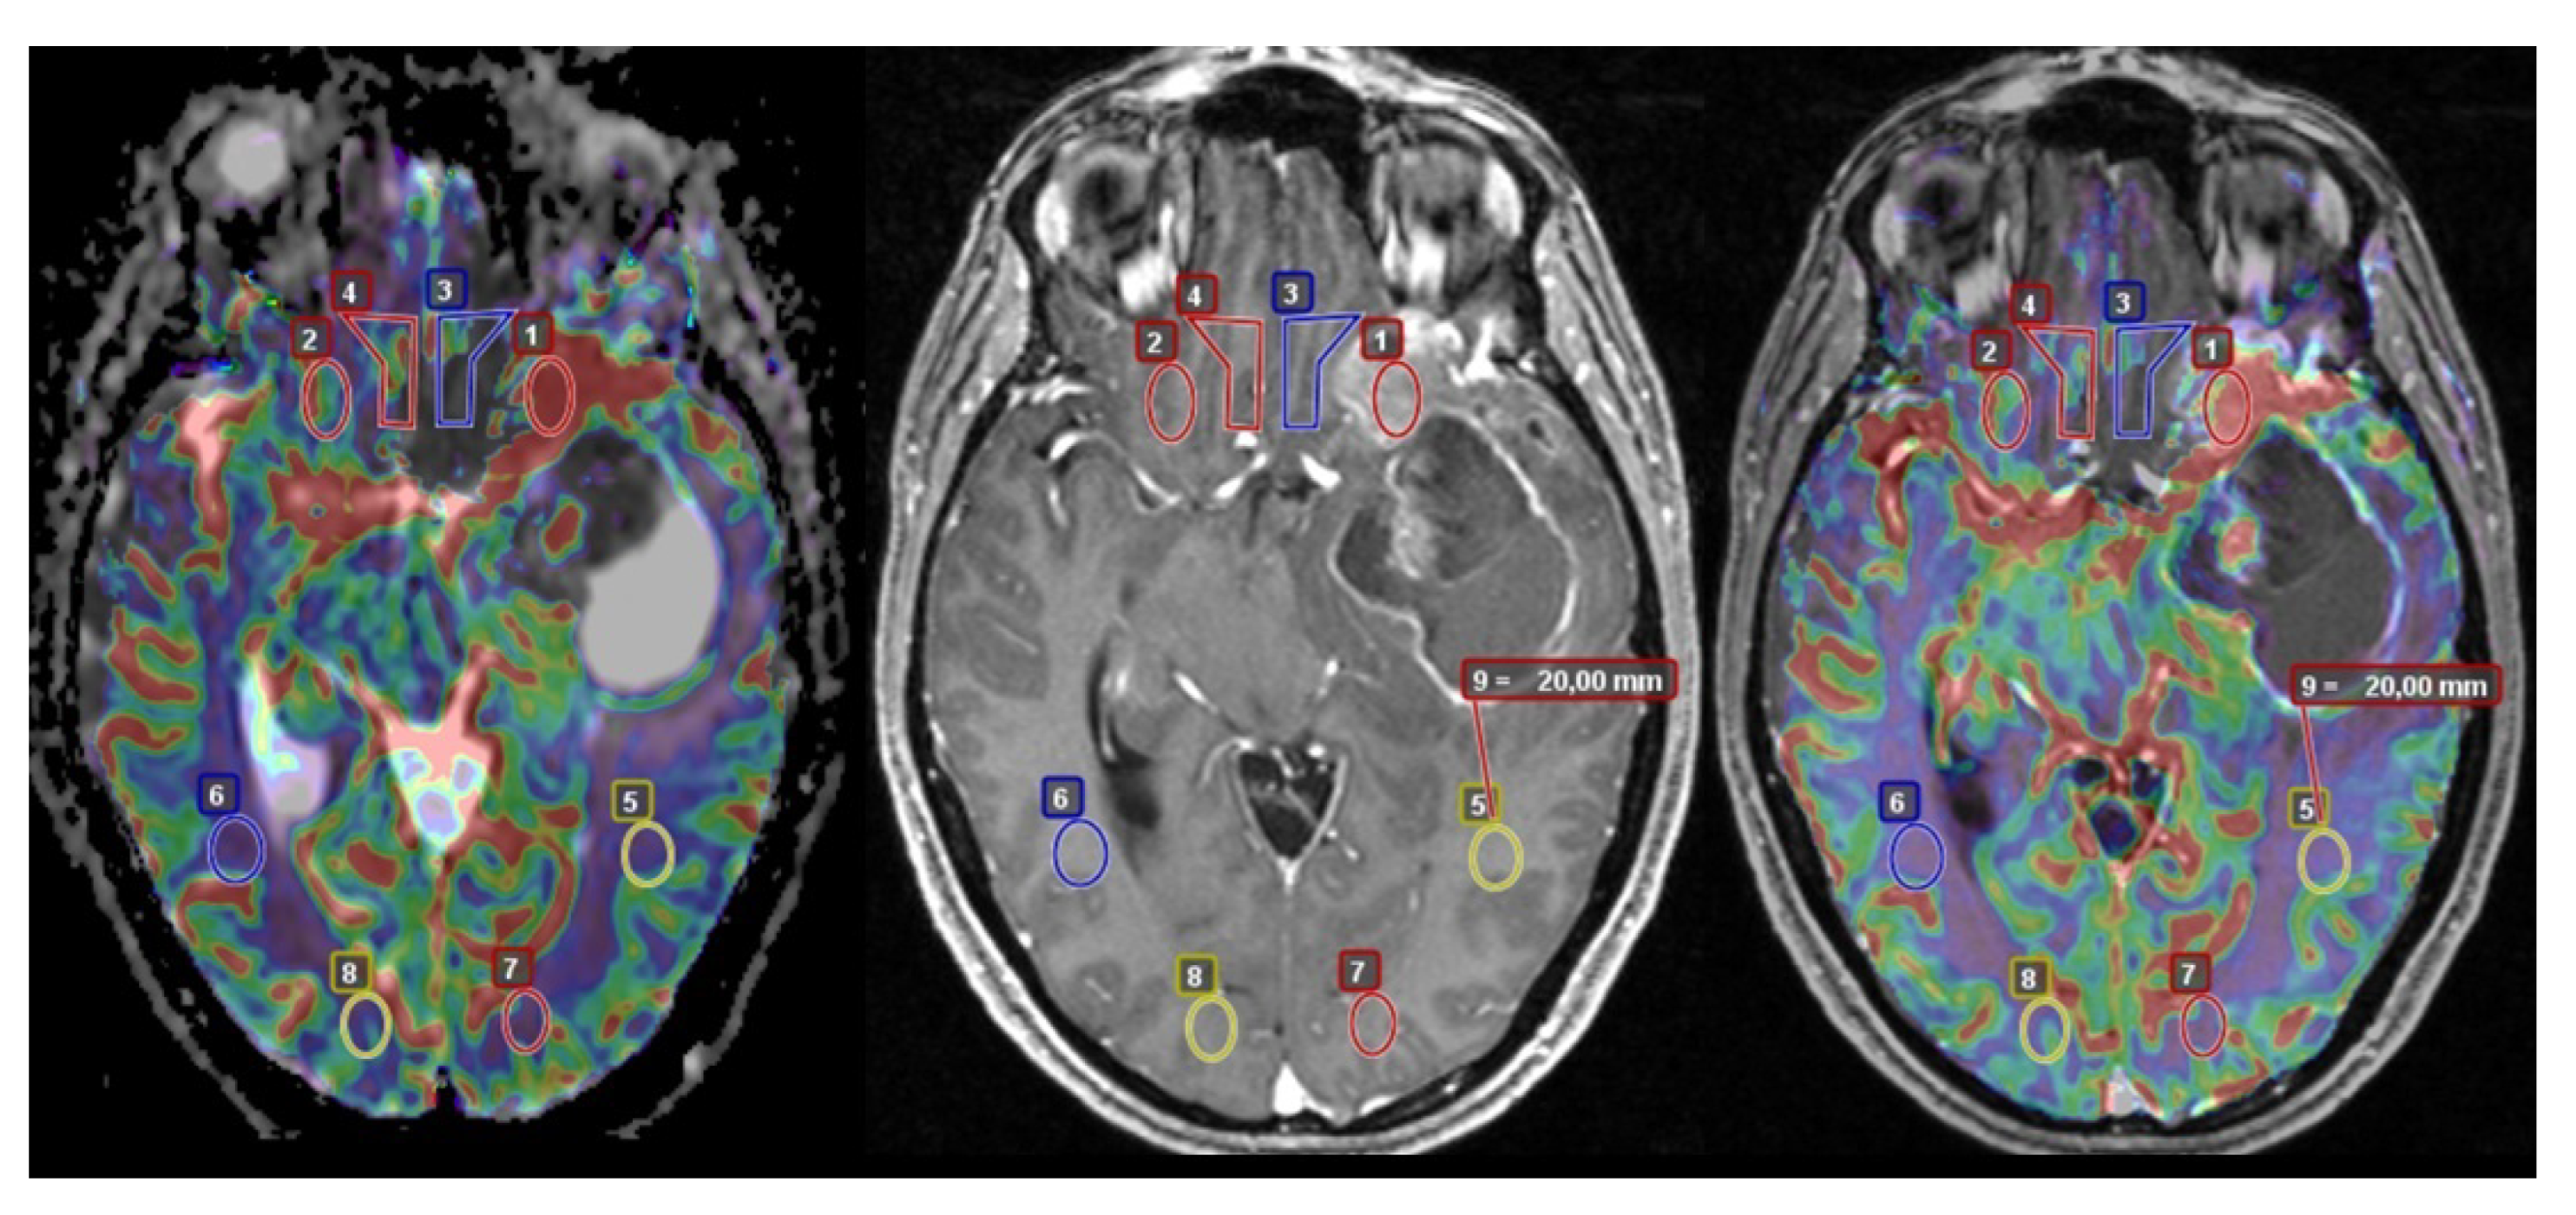

2.2. Image Acquisition and Analysis